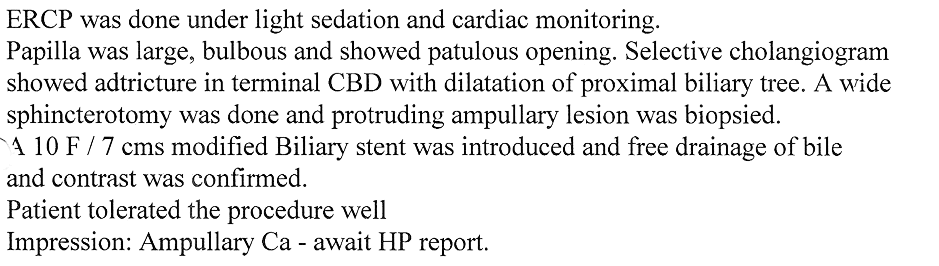

GALL BLADDER STONES TREATMENT

Endoscopic Retrograde Cholangio Pancreatography is an advanced endoscopic procedure related to

diseases of pancreas and biliary tree. Common indication for ERCP is jaundice due to obstruction

of biliary tube, which drains the bile from the liver into the intestine.

Obstruction can be due to a gallstone, which has slipped into bile tube and has blocked the bile tube.

These Stones can be removed by ERCP, without any surgery being involved.

This procedure is necessary if the patient has stones in the gallbladder and also in bile tube and

is always performed before Laparoscopic removal of gallbladder. Cancer of the gallbladder, biliary tree, pancreas,

duodenum or obstruction by lymph nodes can be responsible for jaundice and can be very effectively

treated by ERCP without any need for surgery.

This technique is important in these conditions as majority of the patients coming for jaundice are at an advanced stage of cancer and need palliative treatment to give relief from severe itching and jaundice. Infection or narrowing in the biliary tree can be treated by ERCP.

Common Biles Duct Stones

Common Biles Duct Stones

Cancer of the Bile Tube in Duodenum

Impacted Stone in Common Bile Duct

Chronic Pancreatitis is condition which can result in recurrent attacks of persistent and severe pain.

This can be due to presence of stones or narrowing of the pancreatic duct and can be treated by ERCP.

Pancreatic pseudocyst / collection of fluid is a complication of pancreatitis, which results

in abdominal pain, vomiting, fever etc. It is a serious condition which can be treated by ERCP.

Treatment of Chronic Pancreatitis by Stent

Most of the lesions of biliary system and pancreas were treated earlier by surgery with its own complications, but now with ERCP these conditions can be treated without any surgery and morbidity and mortality related to surgery, and as a cheaper option for surgery and has become treatment of choice for the same.